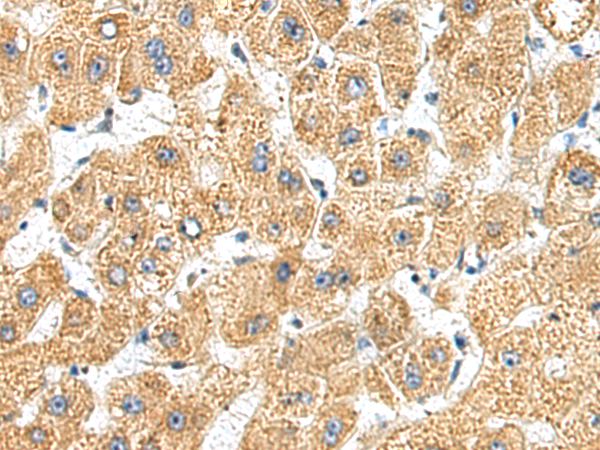

分类: 科研抗体货号: P01939别名: C5FW; TRB2; GS3955应用: IHC反应种属: Human, Mouse